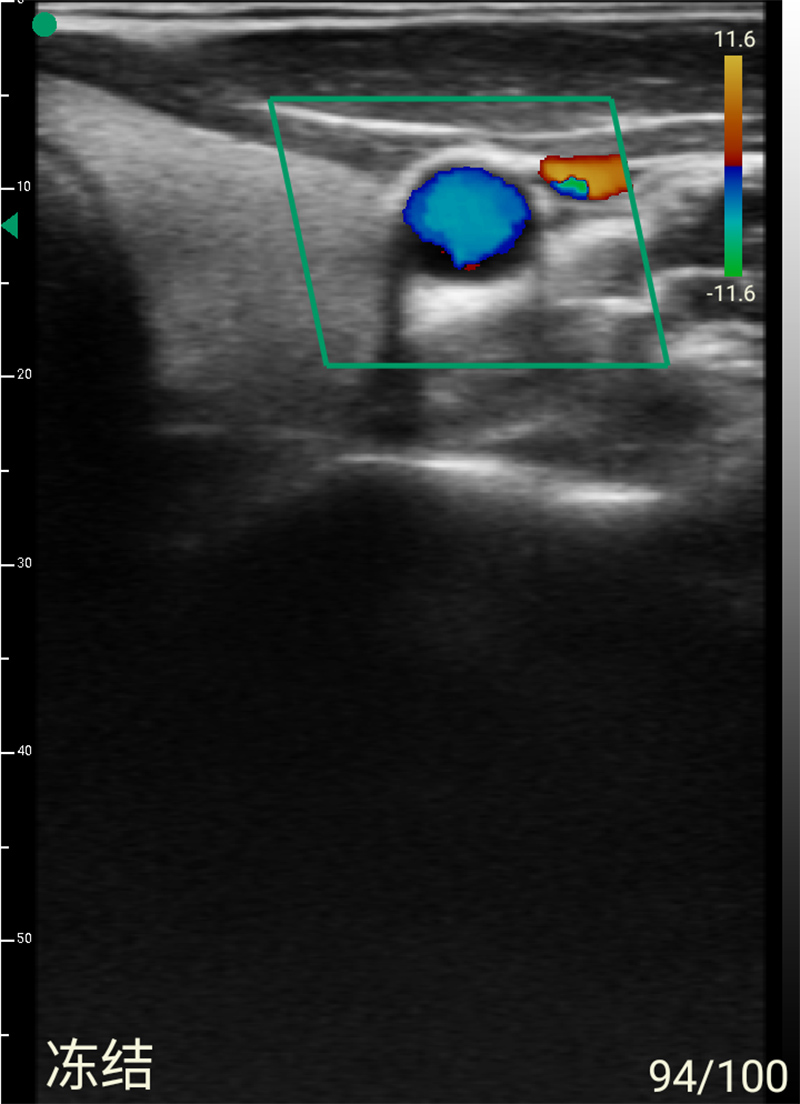

- Display mode: B, B/M, B+Color, B+PDI, B+PW

- Probe frequency: Linear 7.5MHz/10MHz

- Scan depth: Linear 20/30/40/55mm

- Scan width: Linear 40mm